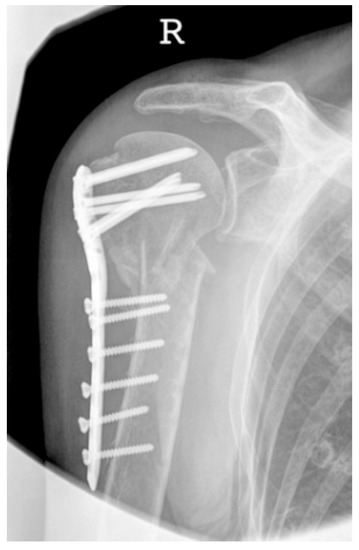

| Complication Type | Exemplary Images by X-rays or Pattern Images | Definition |

|---|---|---|

| 2c | ![]() | Type 2c is defined by a severe varus displacement (>20°) of the humeral head, which is associated with a screw cutout at the humeral head in parallel to Type 2a. In contrast to Type 2a, this varus displacement is characterized by an unstable osteosynthesis situation and progression. |

| 3 | ![]() | Type 3 describes a displacement of the angular stable plate osteosynthesis with screw cutout/fracture avulsion in the humeral shaft region, while the humeral head position remains intact. |

| 4 | ![]() | Complication Type 4a is based on the presence of AVN of the humeral head without concomitant destruction of the glenoid articular surface due to an associated screw cutout through the humeral head cortex. |

| 4b | ![]() | Complication Type 4b is also based on the presence of an AVN of the humeral head combined with a destruction of the glenoid articular surface due to the associated screw cutout through the humeral head cortex. |